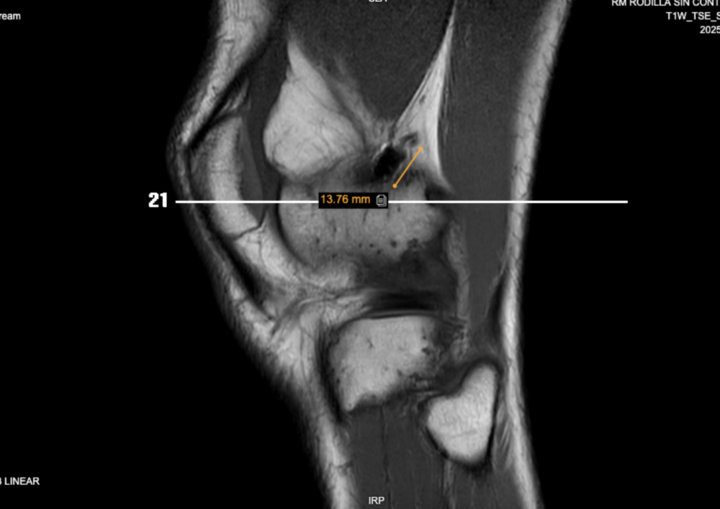

The femoral plasty screw protrudes 15 mm from the posterior femoral cortex. Is this normal or can it cause symptoms? Thanks! https://www.cmrad.com/cases/1711855257

https://www.cmrad.com/cases/1711855257